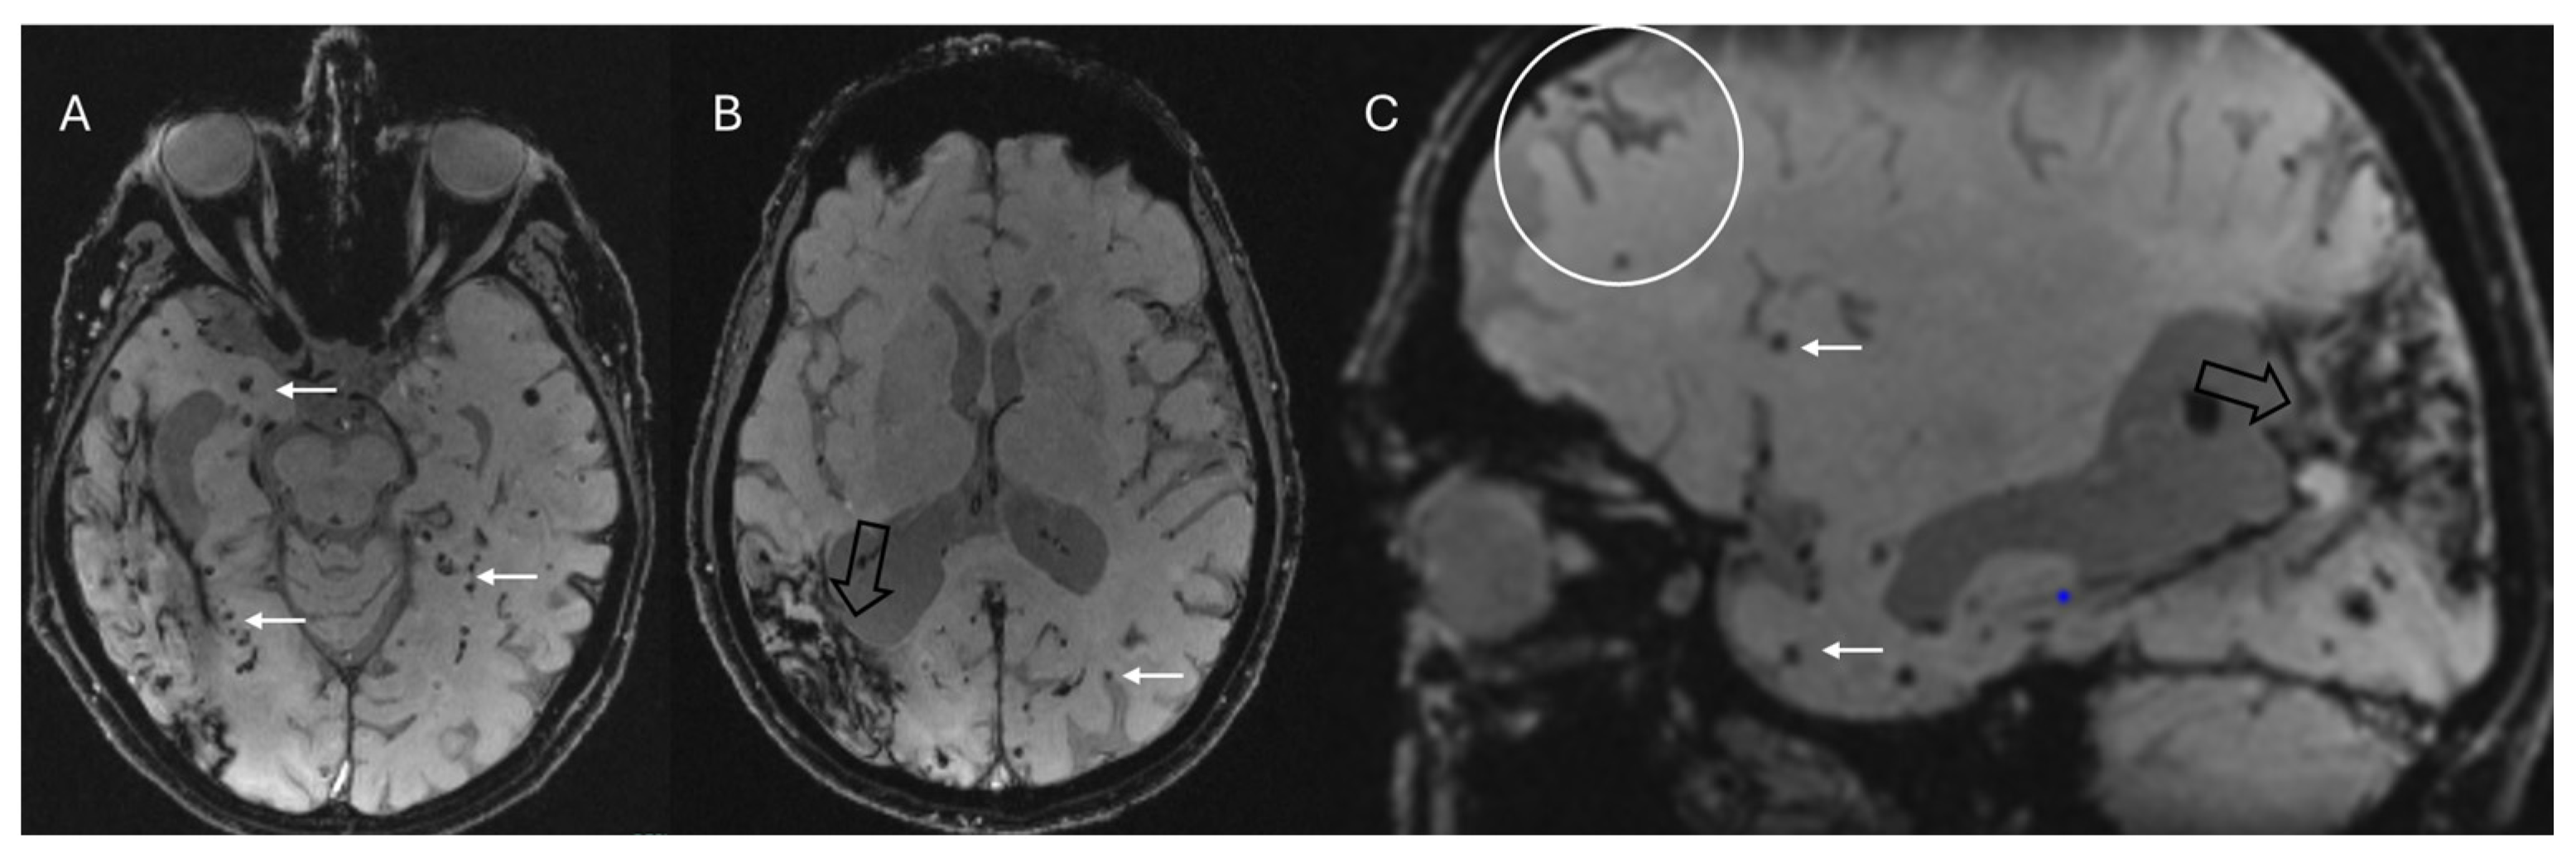

4.3. Cerebral Amyloid Angiopathy

4.4. Other Conditions

- Linn, J.; Halpin, A.; Demaerel, P.; Ruhland, J.; Giese, A.; Dichgans, M.; van Buchem, M.; Bruckmann, H.; Greenberg, S. Prevalence of superficial siderosis in patients with cerebral amyloid angiopathy. Neurology 2010, 74, 1346–1350. [Google Scholar] [CrossRef] [PubMed]

- Lopes, P.A.; Raposo, N.; Charidimou, A.; Zotin, M.Z.; Gurol, M.E.; Greenberg, S.; Viswanathan, A. SWI versus GRE-T2*: Assessing cortical superficial siderosis in advanced cerebral amyloid angiopathy. Rev. Neurol. 2024, 180, 532–538. [Google Scholar] [CrossRef]

- Charidimou, A.; Boulouis, G.; Frosch, M.P.; Baron, J.-C.; Pasi, M.; Albucher, J.F.; Banerjee, G.; Barbato, C.; Bonneville, F.; Brandner, S.; et al. The Boston criteria version 2.0 for cerebral amyloid angiopathy: A multicentre, retrospective, MRI–neuropathology diagnostic accuracy study. Lancet Neurol. 2022, 21, 714–725. [Google Scholar] [CrossRef]

| Cerebral amyloid angiopathy | Cortical or cortico–subcortical microbleeds | Small (2–10 mm), multiple (≥2), round or ovoid, and uniformly hypointense, primarily located in the frontal and parietal lobes (usually sparing the basal ganglia, assisting in the differential diagnosis with hypertensive microangiopathy) |

| Convexity subarachnoid hemorrhage/cortical superficial siderosis | Curvilinear regions of signal drop-out localized to one or more sulci | |